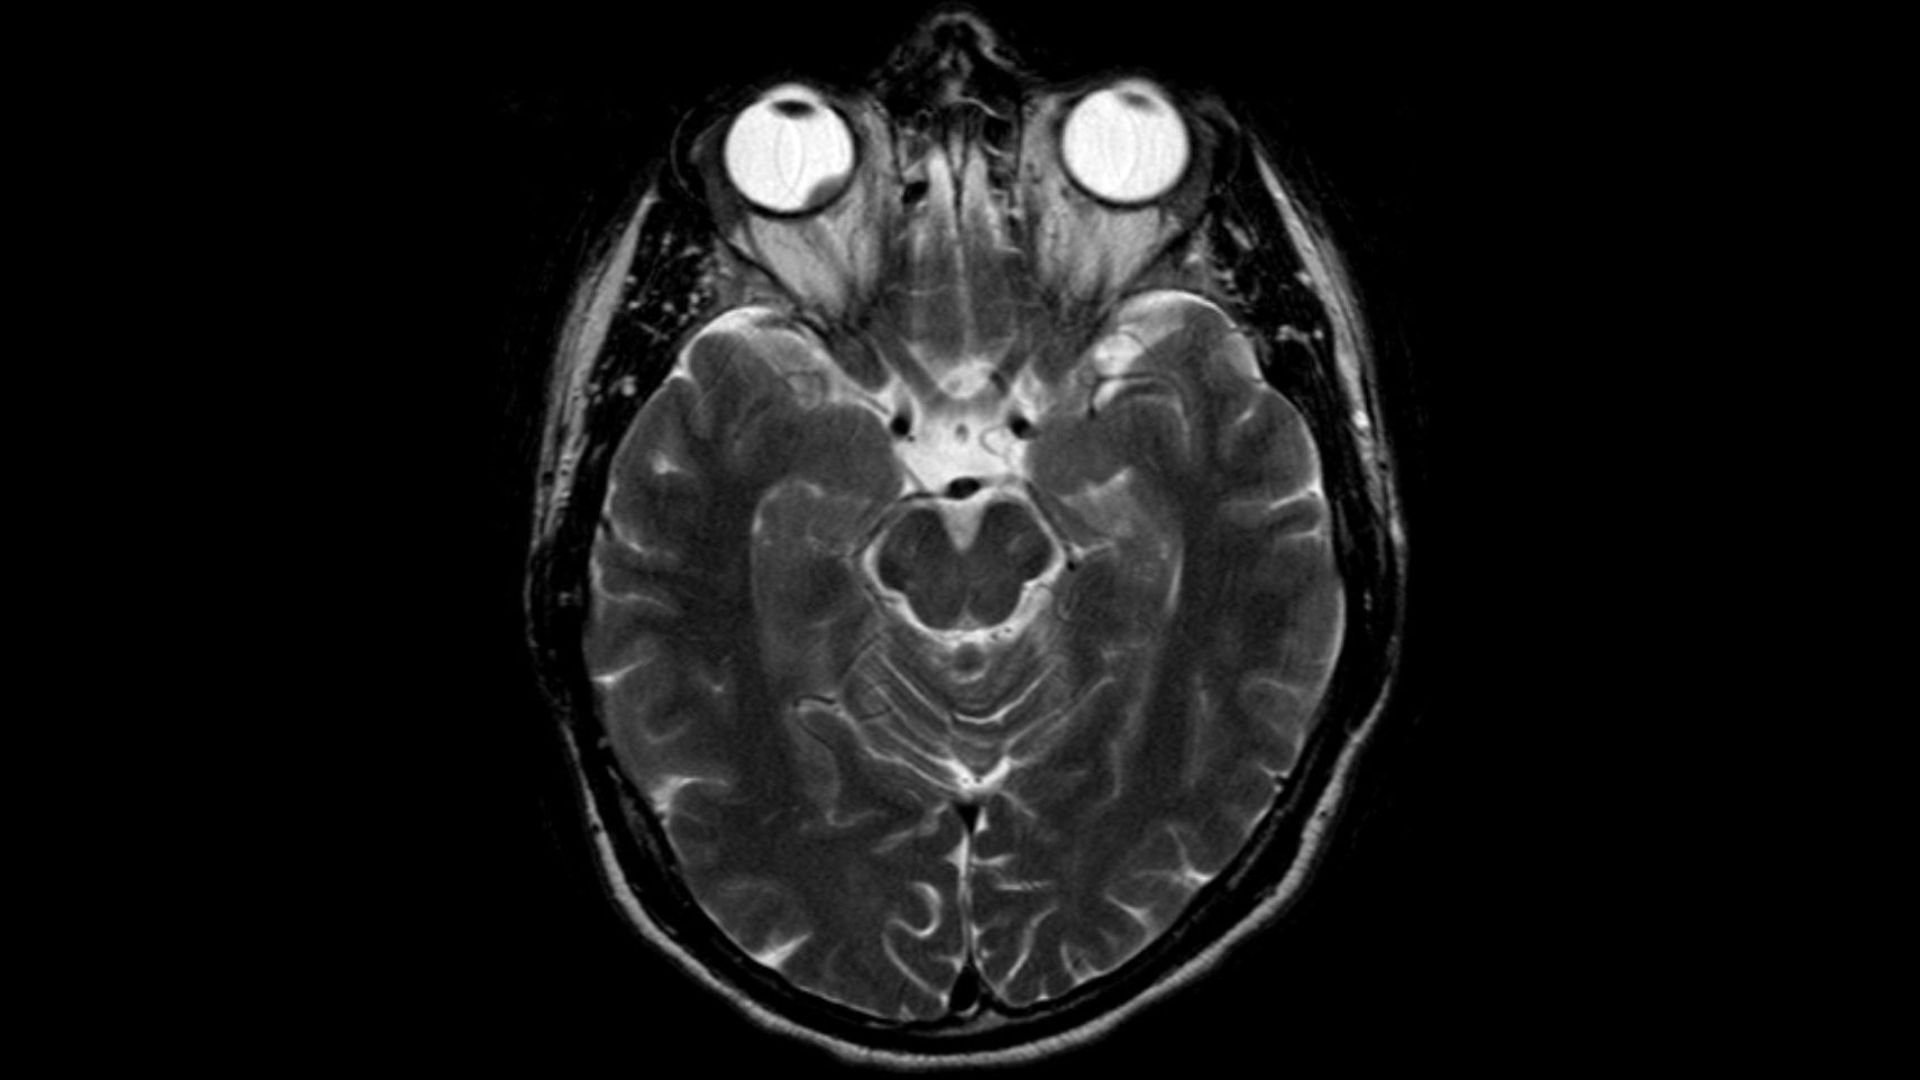

Malignes Melanom an Hirnhaut + Auge

Melanome der Aderhaut sind die häufigsten primären Tumore am Auge. Das Bindehautmelanom ist hingegen sehr selten.

Aderhautmelanom im MRT -

Hellerhoff (https://commons.wikimedia.org/wiki/File:Aderhautmelanom_MRT_T2_axial.jpg), „Aderhautmelanom MRT T2 axial“, https://creativecommons.org/licenses/by-sa/4.0/legalcode

CC BY-SA 4.0